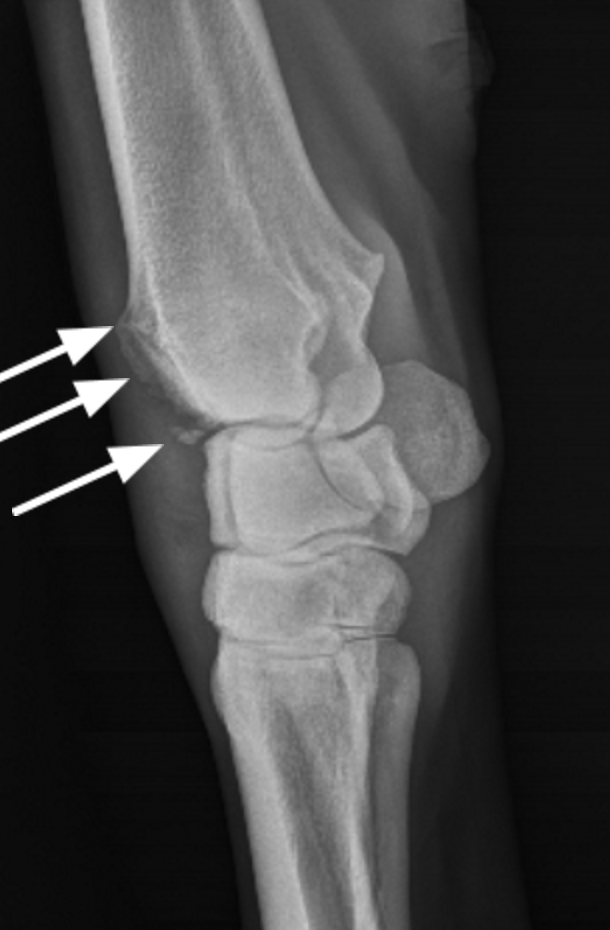

Equine Knee Bone Spurs Bone spur is a term used to describe sharp bony projections that are visible on x rays at the joint margins of affected horses. Our gelding's broken hock has healed with what the veterinarian calls bone spurs. Equine bone spur management is vital in resolving horse bone spurs naturally. Bone spurs in horses are bony outgrowths that form on joints and bones, often due to trauma or degenerative joint diseases. Bone spur is a term used to describe sharp bony projections that are visible on x rays at the joint margins of affected horses. Equine athletes — those beautiful horses who compete in races, rodeos and other events — can suffer any number of medical issues. He believes the spurs could be rubbing against our gelding's tendon, causing pain. The carpus (knee) actually involves 3 joints, any of which could be. This can result in the formation of bony protrusions, called osteophytes or bone spurs, around the affected joint. A bone spur forms near the edge of a joint surface. The joint may also produce excessive synovial fluid, known as joint. One common affliction that causes. The cannon bone and splint bones make up the metacarpus in the horse. If you are curious about the actual appearance and origins of these spurs, read on.

Osteoarthritis both knee . film xray AP ( anterior posterior ) of Equine Knee Bone Spurs Bone spur is a term used to describe sharp bony projections that are visible on x rays at the joint margins of affected horses. A bone spur forms near the edge of a joint surface. The cannon bone and splint bones make up the metacarpus in the horse. The carpus (knee) actually involves 3 joints, any of which could be.. Equine Knee Bone Spurs.